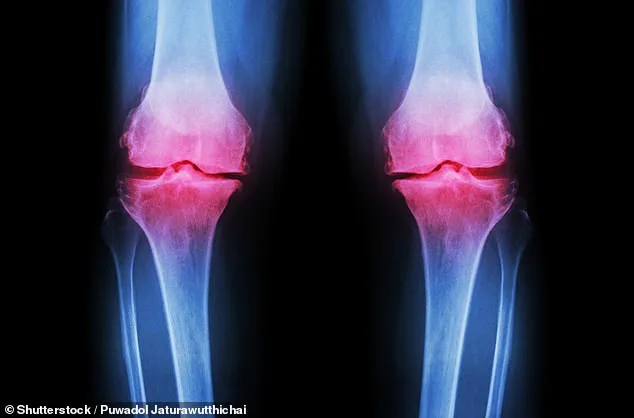

Groundbreaking new knee pain treatment for debilitating joint disease offers hope to 32 million Americans. Scientists at Columbia University have developed a revolutionary approach to treating osteoarthritis by growing a living human knee in the lab. This innovation involves creating a 3D-printed scaffold from biodegradable material, which is then seeded with bone and cartilage cells. Over approximately a year, these cells regenerate natural cartilage and bone tissues, while the scaffold dissolves, resulting in a fully functional lab-grown knee. Researchers suggest this could be transplanted into patients, offering a permanent solution to the agonizing condition. This research represents one of the latest breakthroughs in transforming care for osteoarthritis, a debilitating disease where protective cartilage in joints gradually deteriorates, causing pain, stiffness, and loss of mobility. Approximately 32 million Americans suffer from the condition, with 14 million specifically affected by knee osteoarthritis, a leading cause of disability in the United States. Currently, there is no cure for the condition, and treatments focus on managing symptoms through exercises, injections, or invasive joint replacements with lengthy recovery periods.